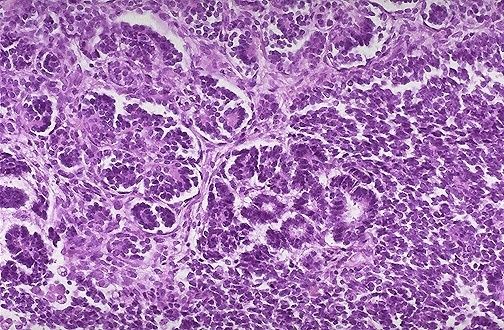

| Carcinoma urotelial microscópico de alta potencia |

Image:

Blad064 (image/jpeg)